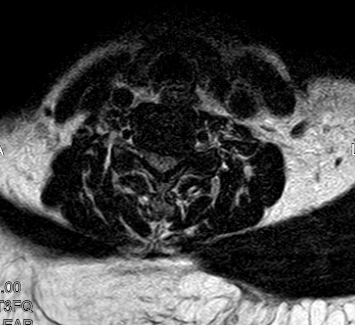

术中

完善相关术前检查,积极术前准备后,陈崇博士和我院骨科团队对患者进行了颈椎后路单开门椎管扩大成形减压术(颈4、5、6),并对颈3和颈7椎板进行潜行减压。